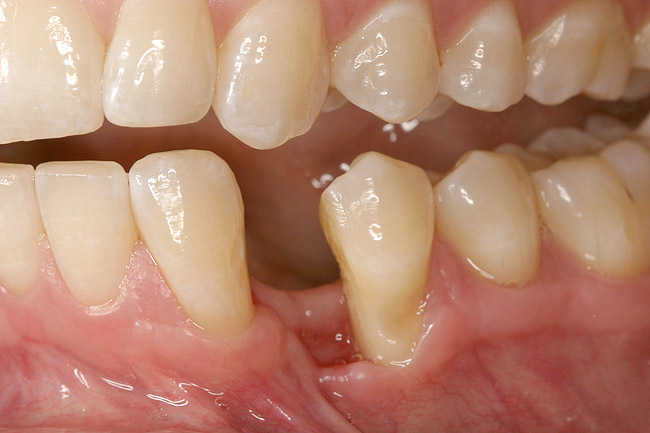

The patient had no medical concerns and had a history of an implant placement in December 2002 when she was 25 years old. In February 2005, she presented with a mobile implant and an associated advanced peri-implantitis. Radiographic review at the initial examination demonstrated significant destruction of the dentoalveolar ridge around the implant as well as around the adjacent natural dentition. Emergency-based treatment involved surgical implant removal only and debridement of the infection (Figure 4 and Figure 5). Following uneventful healing, an advanced ridge defect was apparent at the edentulous site and moderate and advanced attachment loss noted at No. 22D and No. 21M, respectively (Figure 6 and Figure 7). This case demonstrates bone loss of two separate origins: lack of bone because of tooth agenesis and destruction of bone from inflammatory peri-implantitis.

Figure 5  Horizontal ridge defect in site No. 22.

Figure 5